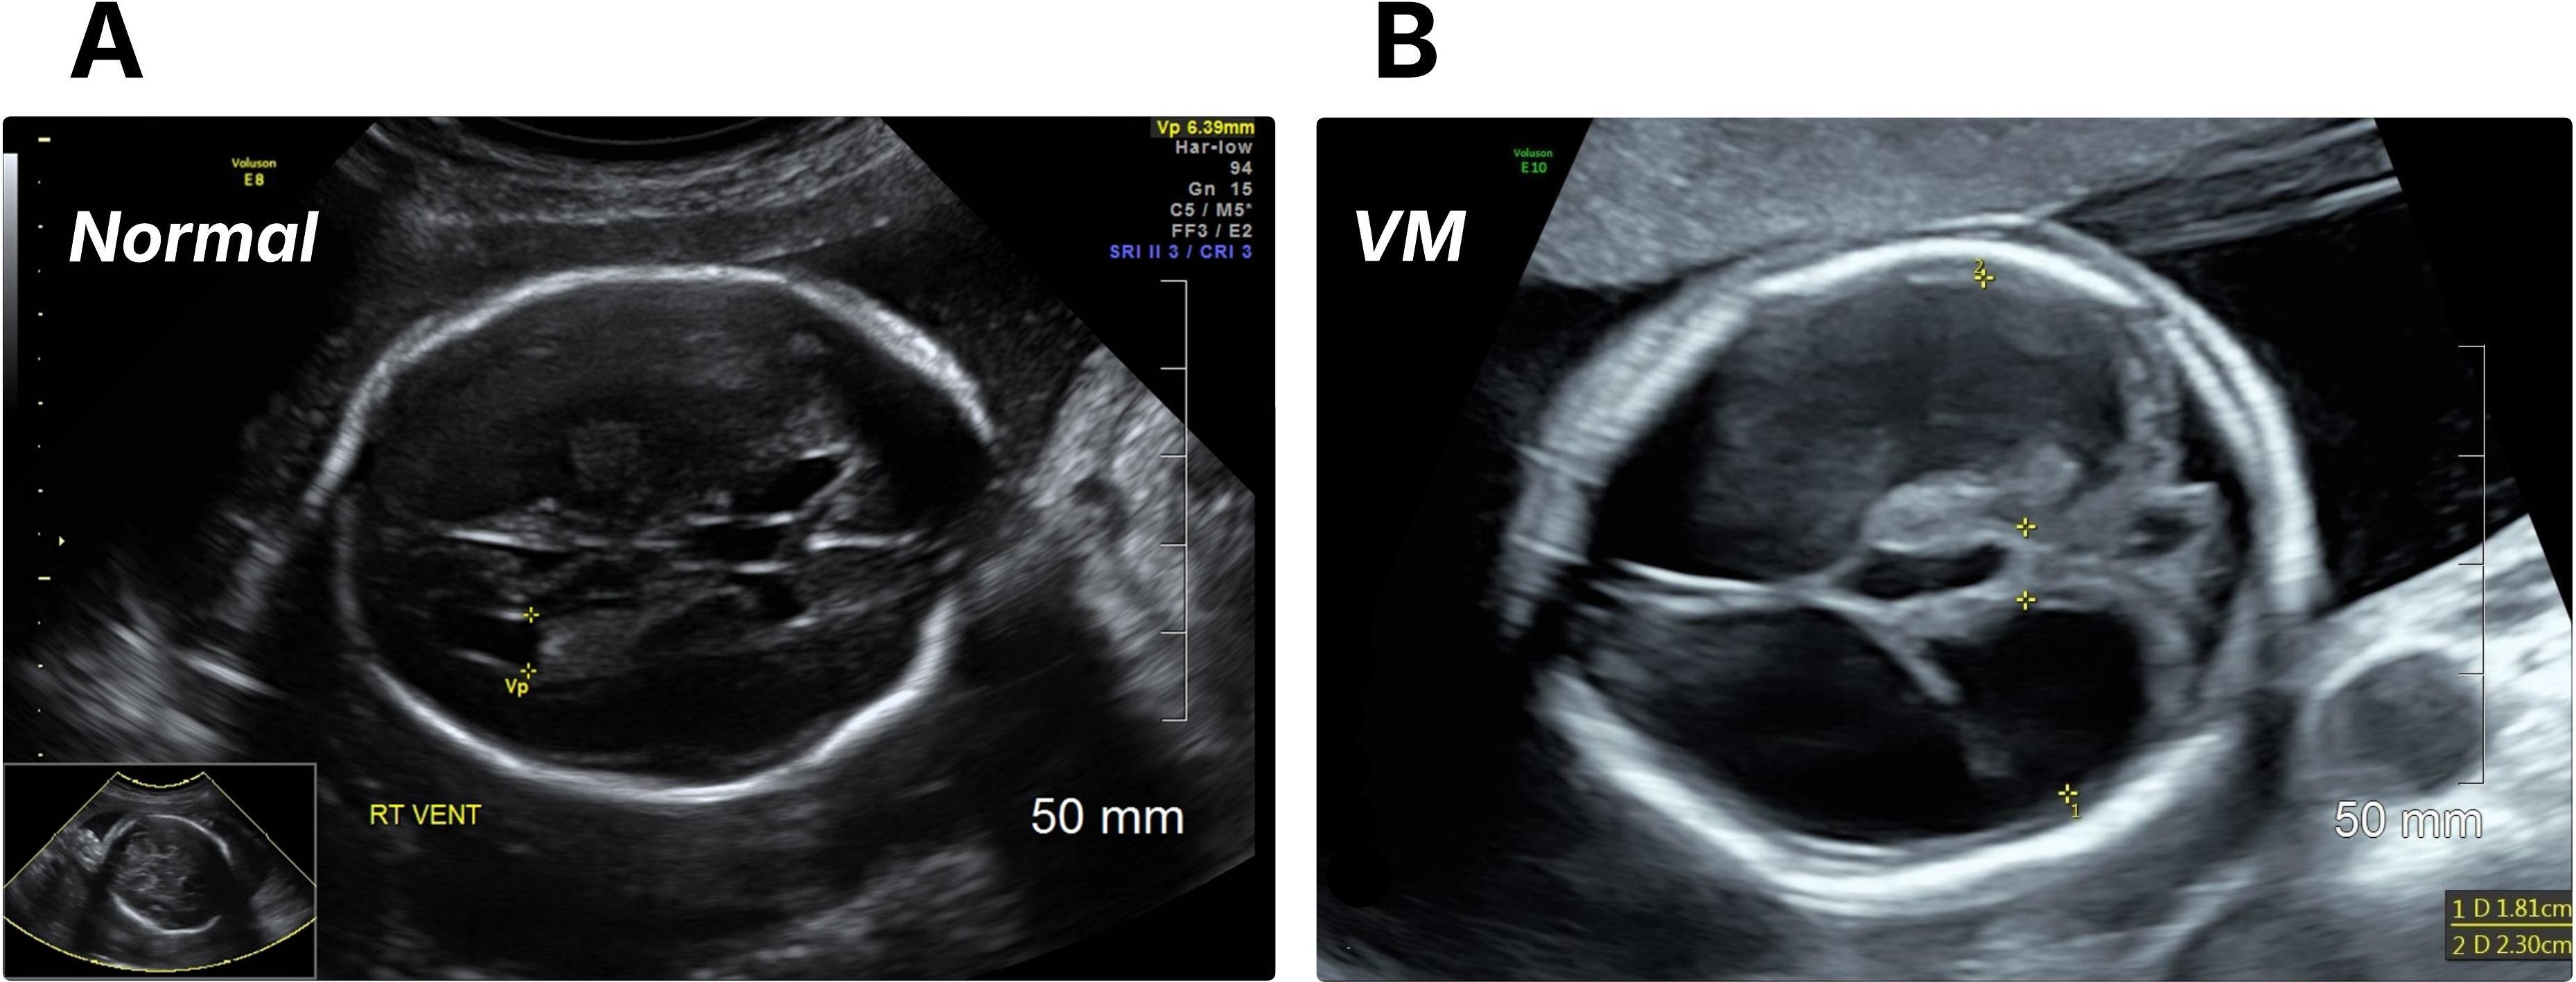

Refer to caption

Figure 1: Prenatal ultrasound comparison of normal and ventriculomegaly (VM) fetal brains. (A) Normal fetal brain showing typical lateral ventricle size and configuration [35]. (B) Fetal brain with VM demonstrating enlarged lateral ventricles.

The study was approved by the Research Ethics Board. This retrospective study included ultrasound images from pregnant individuals with singleton or twin pregnancies obtained between June 2014 and May 2021 at a tertiary hospital in Eastern Ontario, Canada. All images were acquired using the GE Voluson V730, E08, and E10 ultrasound systems by professional obstetric sonographers and interpreted by maternal-fetal medicine specialists. Among these, we selected fetal brain images with or without VM that were obtained between 18 and 24 weeks of gestation (Fig. 1 shows an example of each class). Multiple images were collected from patients who underwent several ultrasound examinations within the designated gestational age (GA) range.